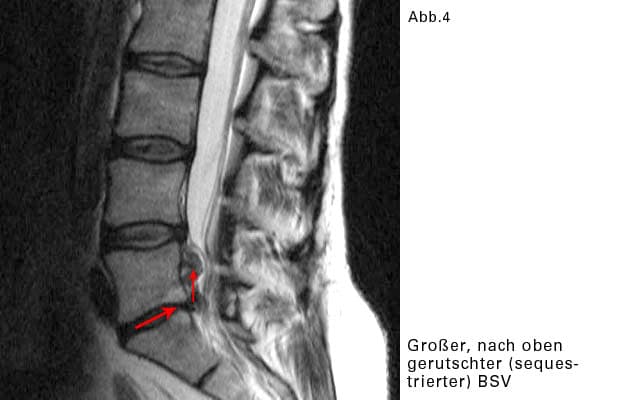

Sequestierter BSV:

Das vorfallende Gallertgewebe löst sich von der restlichen Bandscheibe und rutscht im Wirbelkanal etwas nach oben oder nach unten.